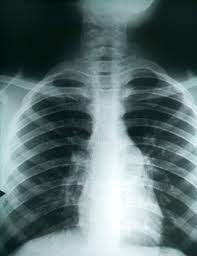

Can Lung Cancer Be Mistaken For Pneumonia / Pneumonia Symptoms Treatment Causes - <p>angie, <br> <br> it took almost 2 months for me to get my diagnosis of advance stage small cell lung cancer in 2016 after being treated for pneumonia.. Thus, many people disregard or miss these common signs of rp: Sometimes, people with pneumonia may have symptoms similar to lung cancer. Pneumonia is an infection of lung tissue usually caused by viruses, bacteria, fungi, and/or parasites. Symptoms and causes of pneumonia are the same regardless of whether you have lung cancer. But the pneumonia density can obscure, or be distal to a cancer.

Aspiration Pneumonitis And Pneumonia Overview Of Aspiration Pneumonia Predisposing Conditions For Aspiration Pneumonia Pathophysiology Of Aspiration Pneumonia from img.medscapestatic.com Radiologic imaging is rarely diagnostic. Boop can mimic lung cancer.and lung cancer can quite easily be mistaken as a pneumonia. Find out more about her lung cancer symptoms and treatment. It can come on gradually or suddenly. Lung cancer and pneumonia both cause the same symptoms and signs that may include: But the pneumonia density can obscure, or be distal to a cancer. Despite the importance of all the causes mentioned by the authors, we would like to emphasize the relevance of fungal infections as an important cause of pulmonary nodules and masses that can mimic lung. Lung cancer is an uncontrolled and uncoordinated overgrowth of the lung tissue.

Is It Common Or Rare For Doctors To Misdiagnose Lung Cancer With Pneumonia Using Chest X Ray Non Contrast Ct Quora from qph.fs.quoracdn.net 50 % lung cancer or 50% pneumonia. Lung cancer is an uncontrolled and uncoordinated overgrowth of the lung tissue. For this reason, lung cancer may be misdiagnosed as conditions such as pneumonia, asthma, tuberculosis, or bronchitis. Radiation pneumonitis symptoms can be very similar to lung cancer symptoms or side effects from other cancer treatments, or they can be mistaken for an infection such as pneumonia. If the condition is misdiagnosed or its symptoms are ignored, a patient may not receive appropriate treatment until the cancer has progressed to an advanced stage. Sometimes, people with pneumonia may have symptoms similar to lung cancer. Malignant tumors trigger inflammation in surrounding normal lung tissue, and they may obstruct. <p>angie, <br> <br> it took almost 2 months for me to get my diagnosis of advance stage small cell lung cancer in 2016 after being treated for pneumonia.